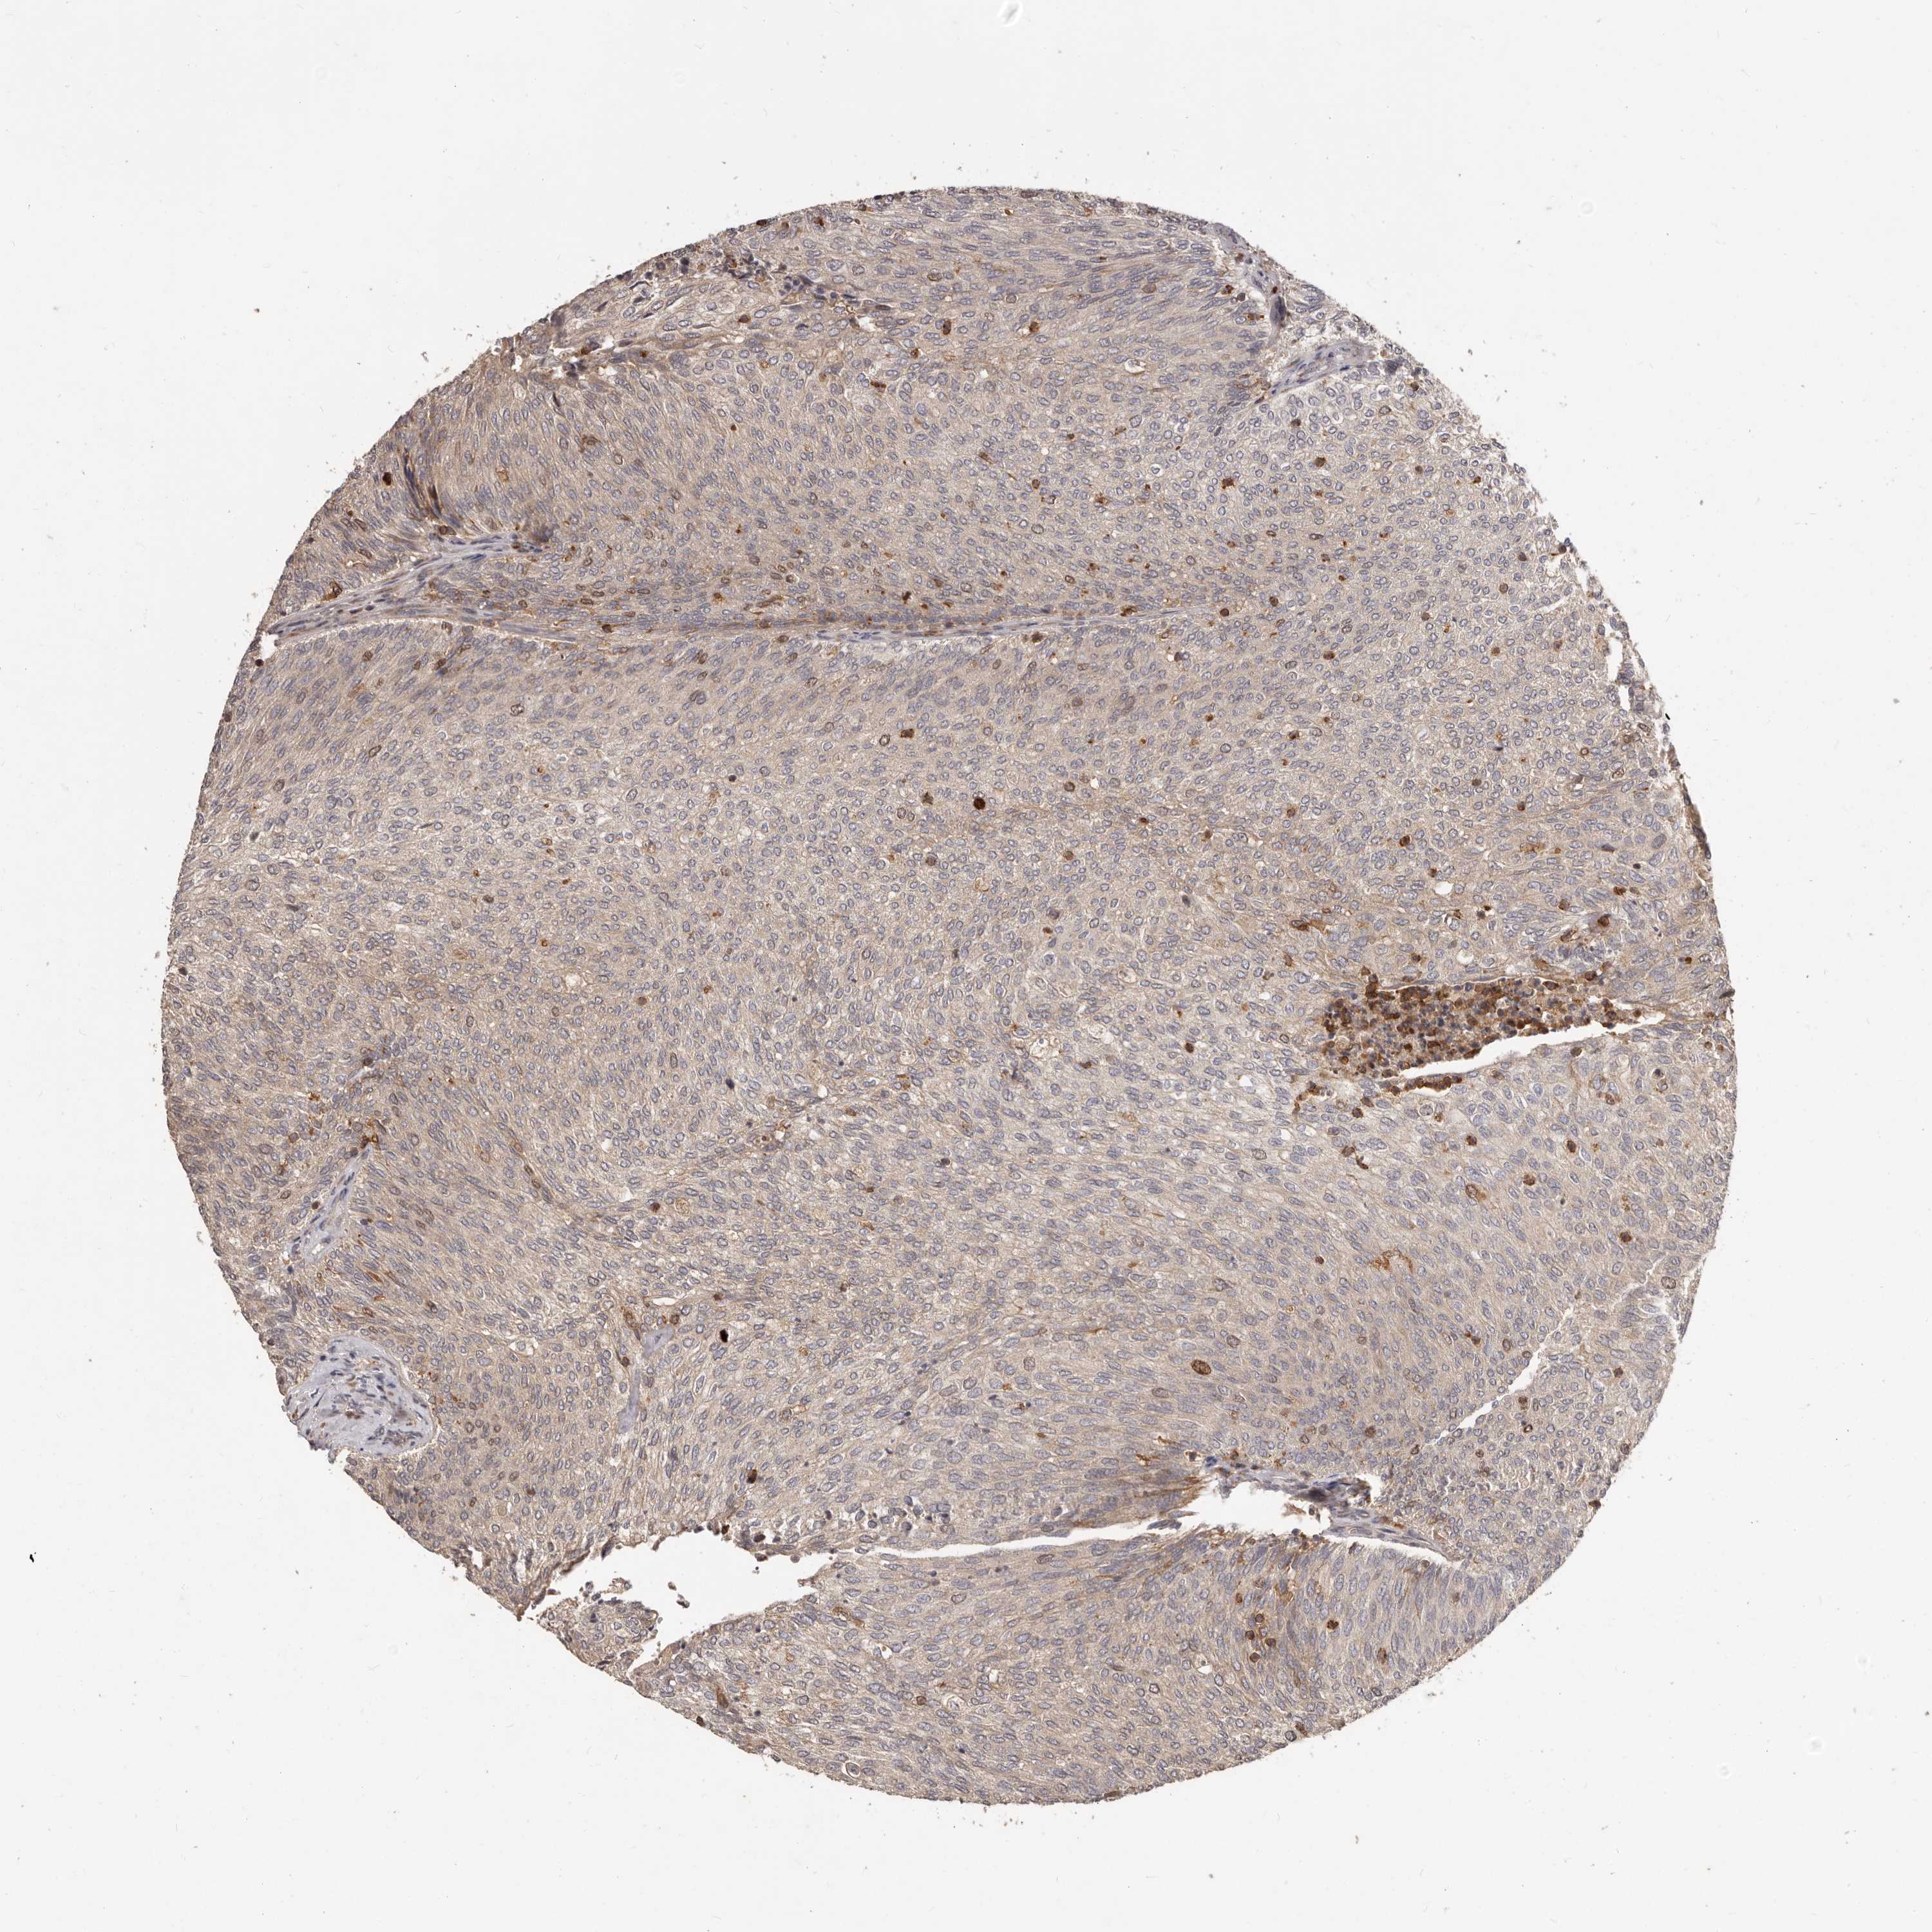

UROTHELIAL CANCER - Protein expressioni

A mouse-over function shows sample information and annotation data. Click on an image to view it in a full screen mode. Samples can be filtered based on level of antibody staining by selecting one or several of the following categories: high, medium, low and not detected. The assay and annotation is described here.

Note that samples used for immunohistochemistry by the Human Protein Atlas do not correspond to samples in the TCGA dataset.

Antibody stainingi

Antibody staining in the annotated cell types in the current human tissue is reported as not detected, low, medium, or high, based on conventional immunohistochemistry profiling in selected tissues. This score is based on the combination of the staining intensity and fraction of stained cells.

Each image is clickable and will lead to virtual microscopy that enables deeper exploration of all samples and also displays staining intensity scores, fraction scores and subcellular localization as well as patient and tissue information for each sample.

Antibody HPA030098

Staining

High

Medium

Low

Not detected

Intensity

Strong

Moderate

Weak

Negative

Quantity

>75%

75%-25%

<25%

None

Location

Nuclear

Cytoplasmic/membranous

Cytoplasmic/membranous,nuclear

Urothelial carcinoma, Low grade

Urothelial carcinoma, High grade